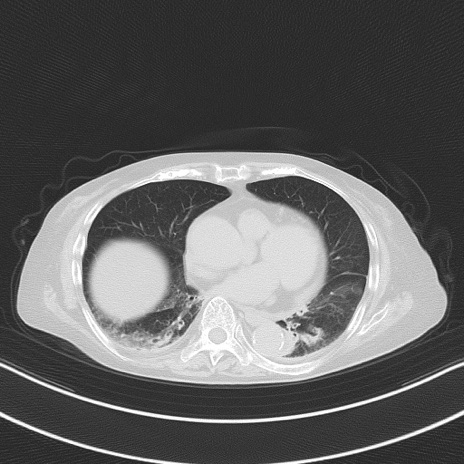

他院CT